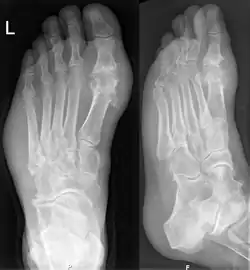

Nach Ablauf mehrerer Anfälle entwickelt sich eine chronische Gicht mit Zerstörung der Gelenke. Charakteristisch sind im Röntgenbild gelenknahe Stanzdefekte in der Spongiosa (innere Anteile des Knochens), der Gelenkkopf weist deutliche Defekte auf. Die Folgen sind Einschränkung der Leistungsfähigkeit, Harnsäurekristallablagerungen in Gelenken, Gelenkdeformation, Nierensteine, Nierenversagen. Wenn die Gicht in die chronische Phase übergeht, werden die akuten Anfälle oft weniger deutlich und weniger schmerzhaft.

Außerdem lassen sich bei chronischem Verlauf der Erkrankung typische Veränderungen der Knochen im Röntgenbild nachweisen (z. B. Gelenkzerstörung und gelenknaher Knochenschwund, Tophi). In der Urografie dient die indirekte Darstellung einzelner Uratsteine der Diagnosestellung (sind im Röntgenbild nicht darstellbar). Schließlich kann bei Unklarheit auch eine direkte Gelenkpunktion bei Vorliegen von Uratkristallen in der Synovialanalyse die Diagnose sichern.